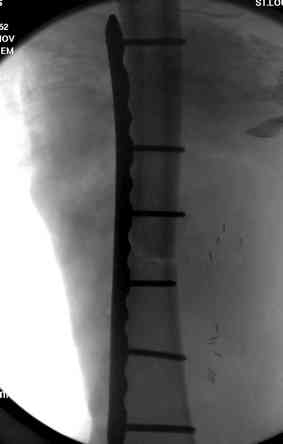

здесь случай с политравмой, перелом зафиксирован  наружным

фиксатором, после третьей irrigation&debridment фиксация бедра

пластиной с последующей кожной пластикой.

Имя     : 1open femur.jpg

Тип     : image/jpeg

Размер  : 14270 байтов

Описание: отсутствует

Url     : http://weborto.net:8080/pipermail/ortho/attachments/20080516/ebe5bb74/attachment-0011.jpg